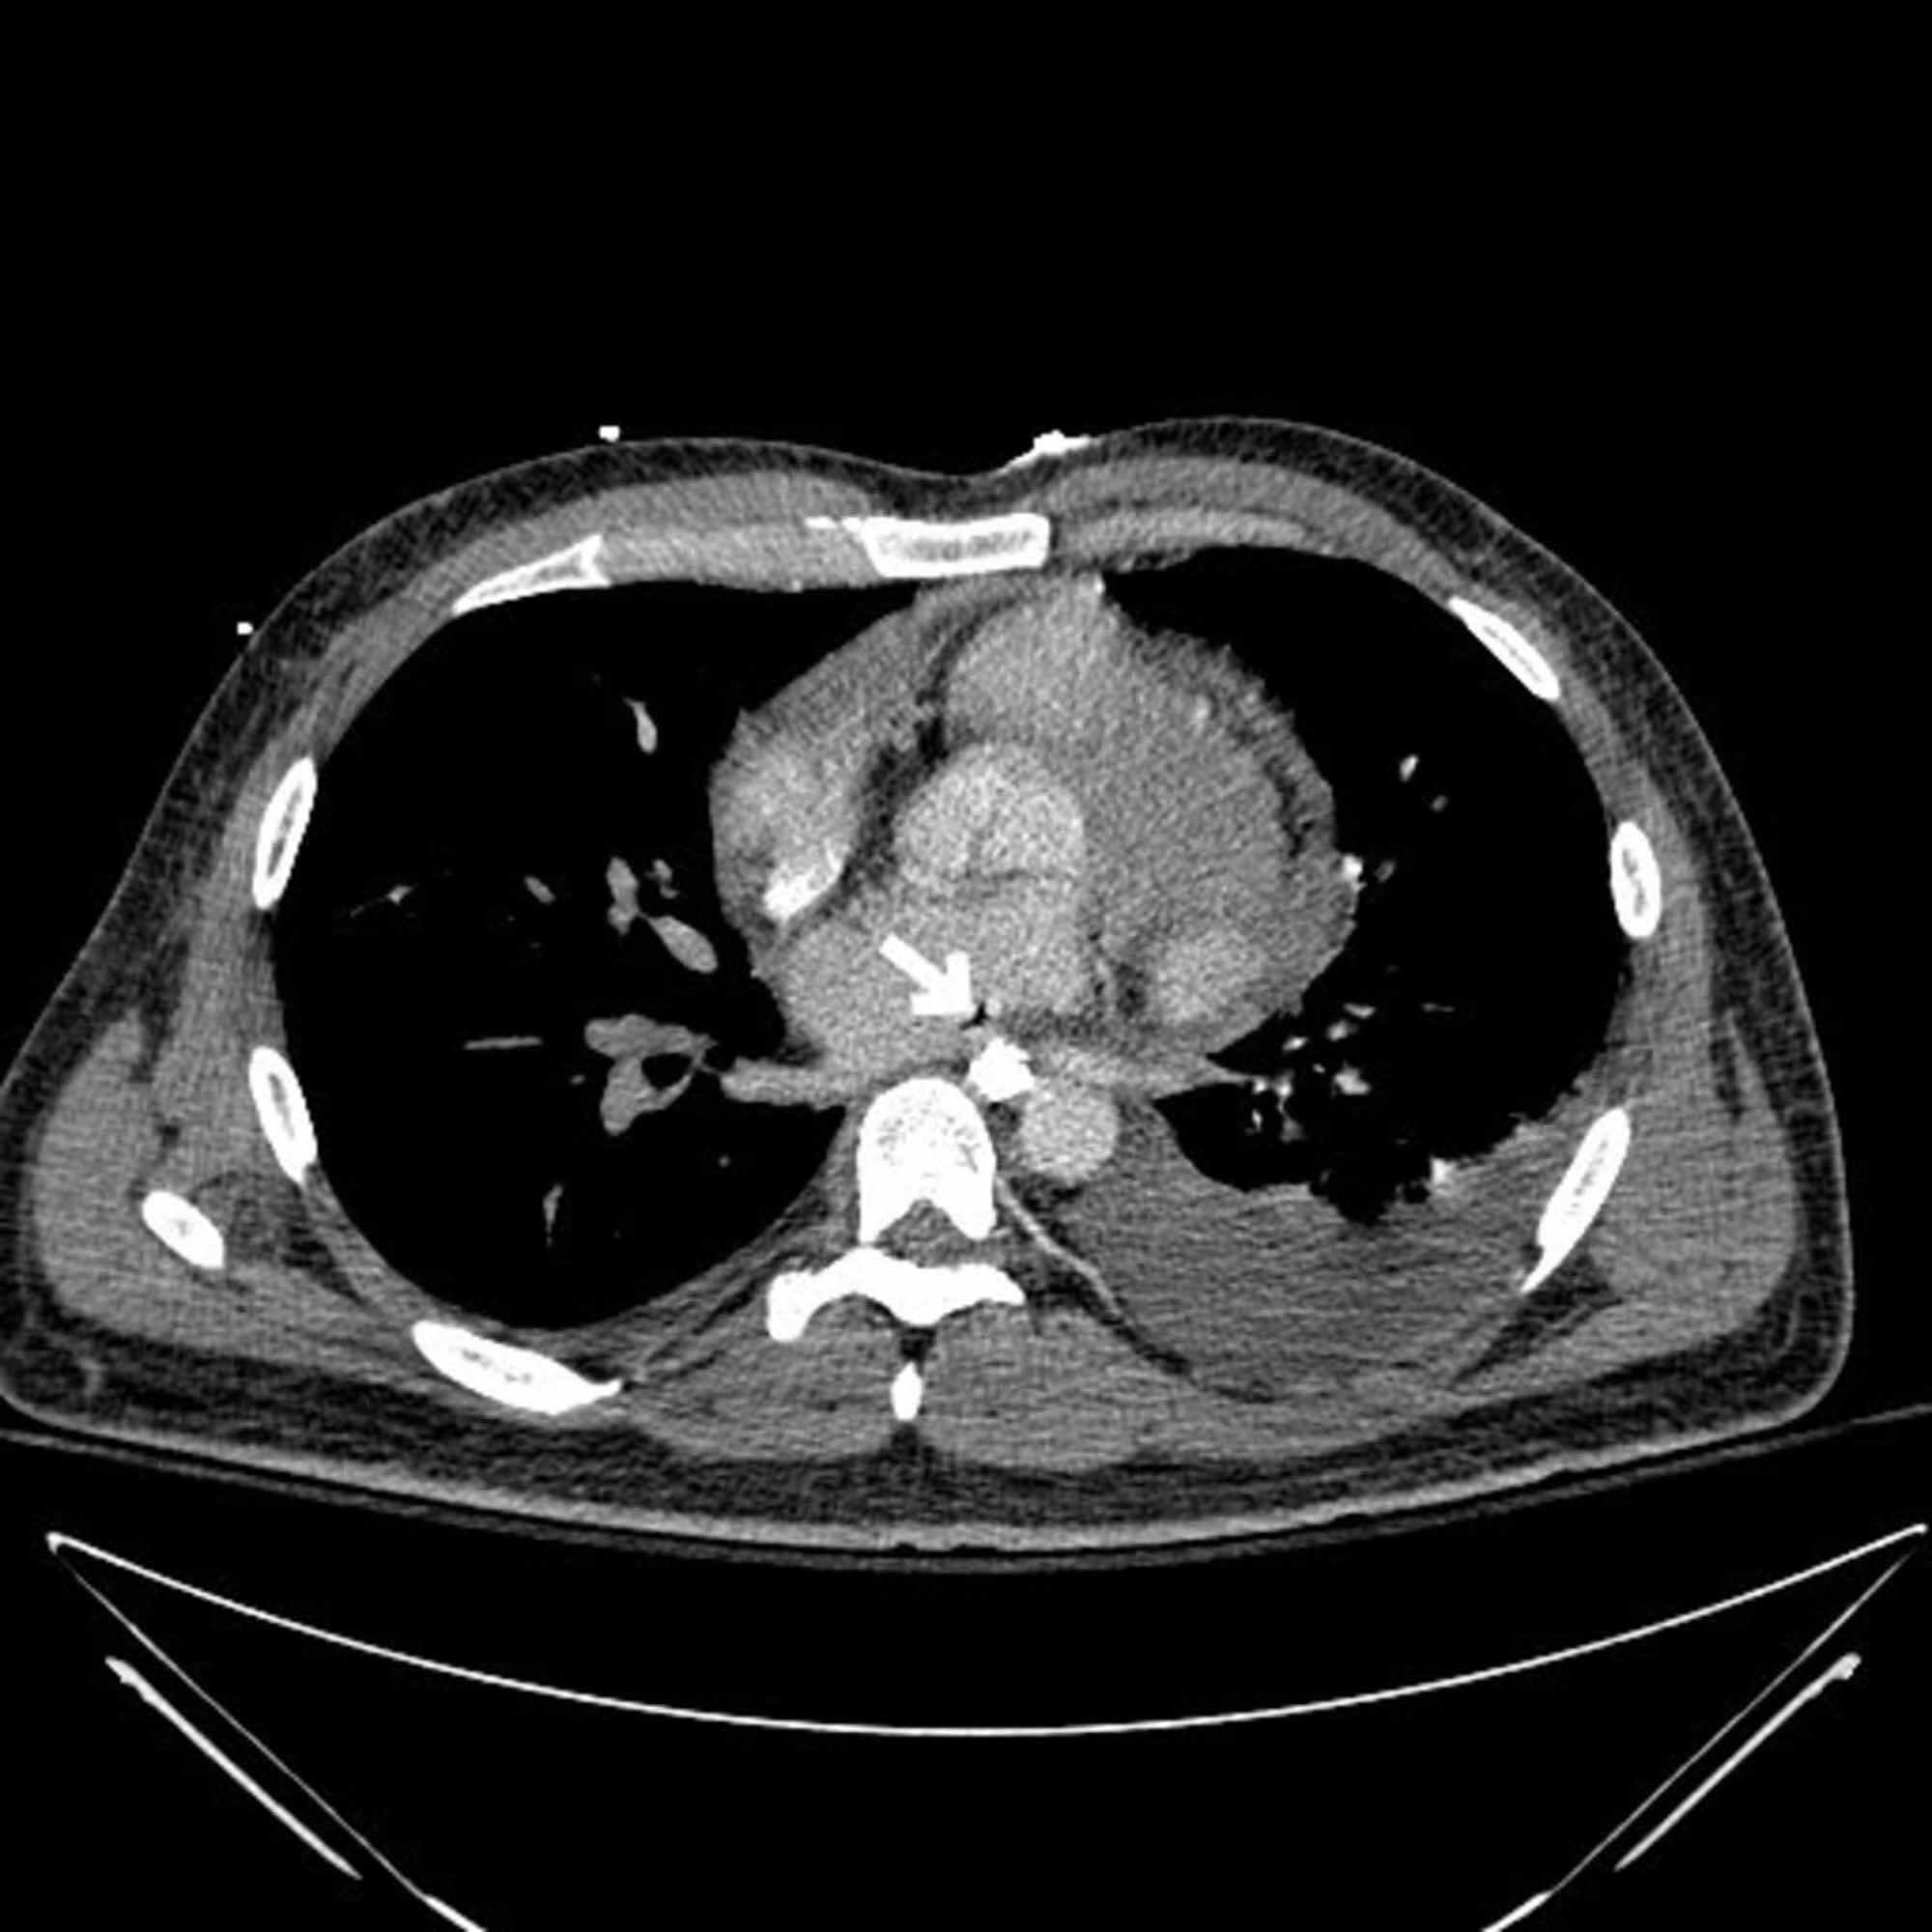

Cureus A Rare Complication of Cardiac Ablation Atrialesophageal Is Esophageal Ablation Painful Far more often, however, rfa. ablation destroys damaged esophageal cells and prevents further progression of barrett’s esophagus. Take this medication as needed for pain. this medication is used for pain. there is also a small risk of esophageal stricturing (narrowing) after rfa, which may require an endoscopic procedure to relieve. this video animation shows use of. Is Esophageal Ablation Painful.

Cureus A Rare Complication of Cardiac Ablation Atrialesophageal Is Esophageal Ablation Painful Ablation therapy is a minimally invasive procedure. Far more often, however, rfa. Take this medication as needed for pain. this medication is used for pain. ablation destroys damaged esophageal cells and prevents further progression of barrett’s esophagus. this video animation shows use of radiofrequency energy in treatment (ablation) of barrett's esophagus and. there is also a. Is Esophageal Ablation Painful.